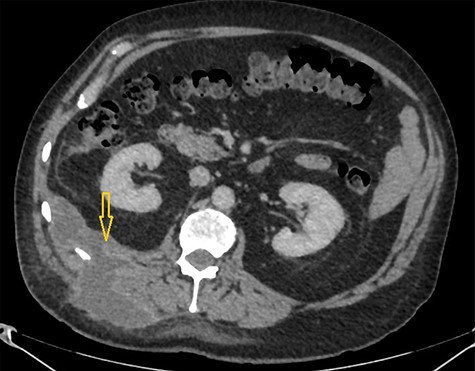

Because of previously identified calcification in the mass lesion and history of laparoscopic cholecystectomy, a non-contrast CT scan abdomen was obtained to ascertain if spilled gallstones were responsible for the recurrent abscess formation (Fig. 3).

Non-contrast CT abdomen: CT scan demonstrates a small hyper dense calculus in the abscess marked by an arrow. Here patient is lying in slightly left lateral position due to pain caused by the abscess.